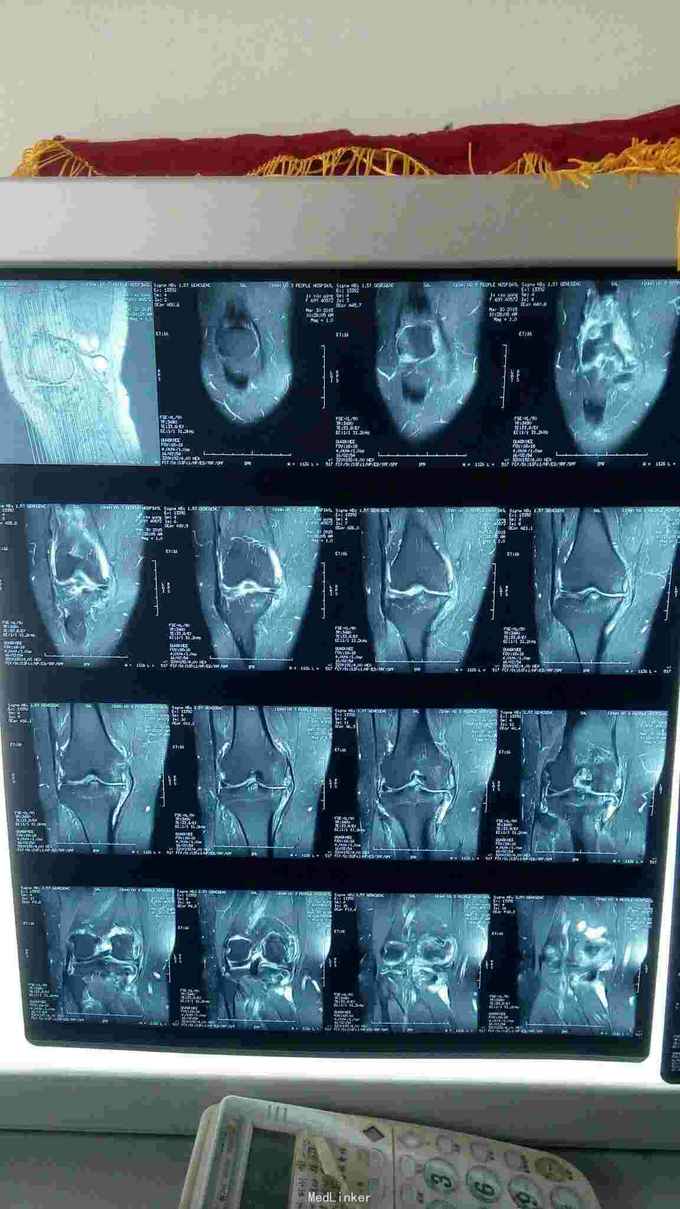

右膝肿胀,皮色皮温正常,伸直10°-屈曲80°,腘窝压痛(+),髌周压痛(+),内外侧间隙压痛(+),MRI示右膝内侧半月板损伤,外侧半月板退行性变,股骨胫骨剥脱性软骨炎,关节腔积液,腘窝囊肿。